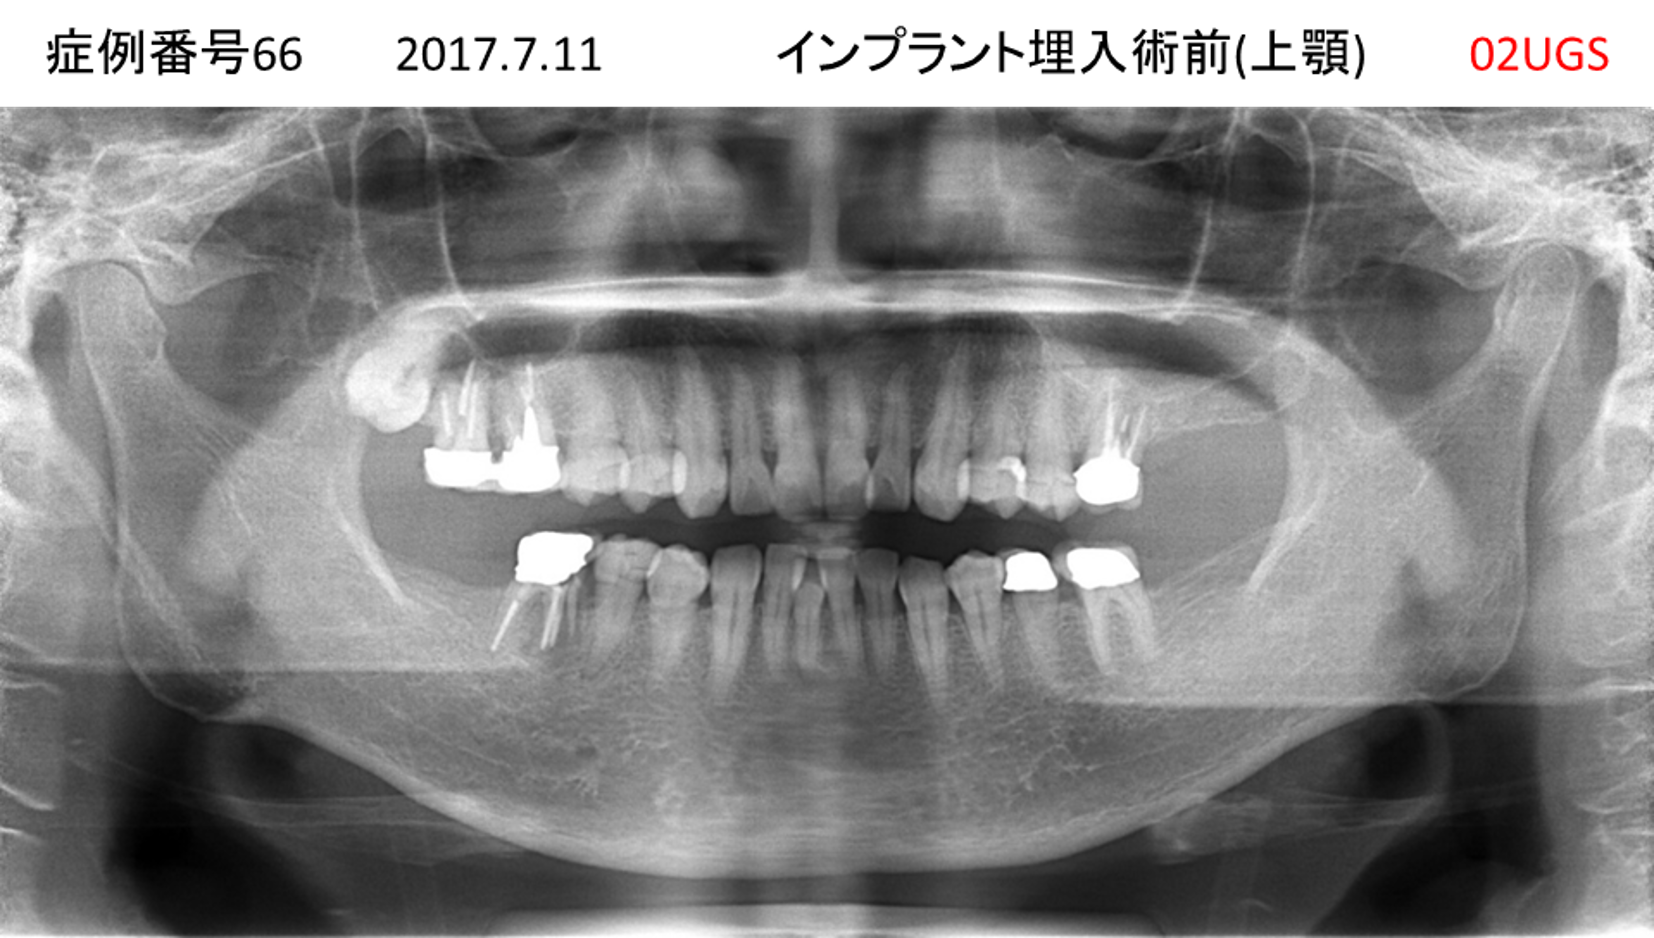

上の前歯が揺れていて痛い患者様のインプラント症例

| 治療名称 |

インプラント |

| 治療費用 |

295万円+税 |

| 治療期間 |

6か月 |

| 患者さんの症状(主訴) |

上の前歯が揺れていて痛い |

| 治療内容 |

抜歯即時インプラント |

| 治療結果 |

痛みがなく、しっかり噛める。 見栄えがとても良い |

| 治療の注意点(リスク/副作用) |

インプラントが壊れたら再治療が必要 |